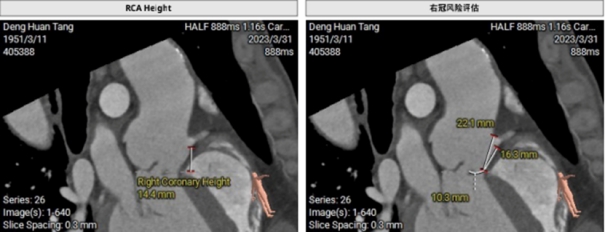

经心脏中心卢才义主任、李龙虎主任团队分析研判:此例患者结合临床明显瓣膜病症状以及在术前心室造影综合评估得出,此例患者为Type0二叶式重度主动脉瓣返流病人,瓣环周长84mm,LVOT周长90.3 mm,瓦式窦长径40.9mm,短径24.4mm,STJ 均径33.1mm,升主动脉均径35.2mm,左冠高度17.5mm,右冠高度14.4mm,下肢入路血管条件可。但CT造影提示主动脉瓣叶脱垂,流出道呈喇叭口状,且窦内钙化较轻缺乏有力锚定,考虑到植入后的人工瓣膜有一定的压缩比,锚定条件可,但不可过深植入,所以本次瓣膜的植入深度和瓣膜的锚定位置情况是本次手术的重要关键点。